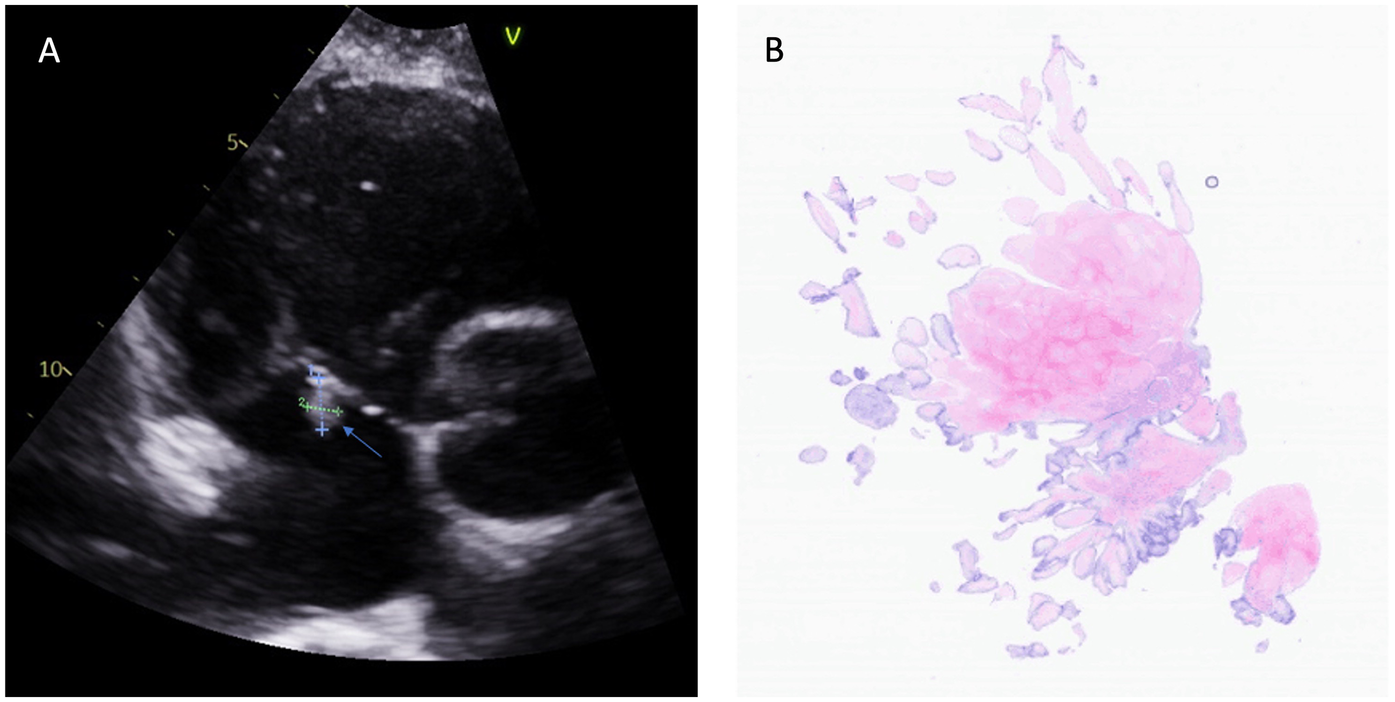

Figure 2

Fibroelastoma on the septal leaflet of the tricuspid valve. (A) Transthoracic echocardiography identified a small, mobile mass on the septal leaflet of the tricuspid valve (indicated by the arrow). (B) Light microscopy (hematoxylin and eosin staining of the mass at 40× magnification) revealed the characteristics of the papillary fibroelastomas.